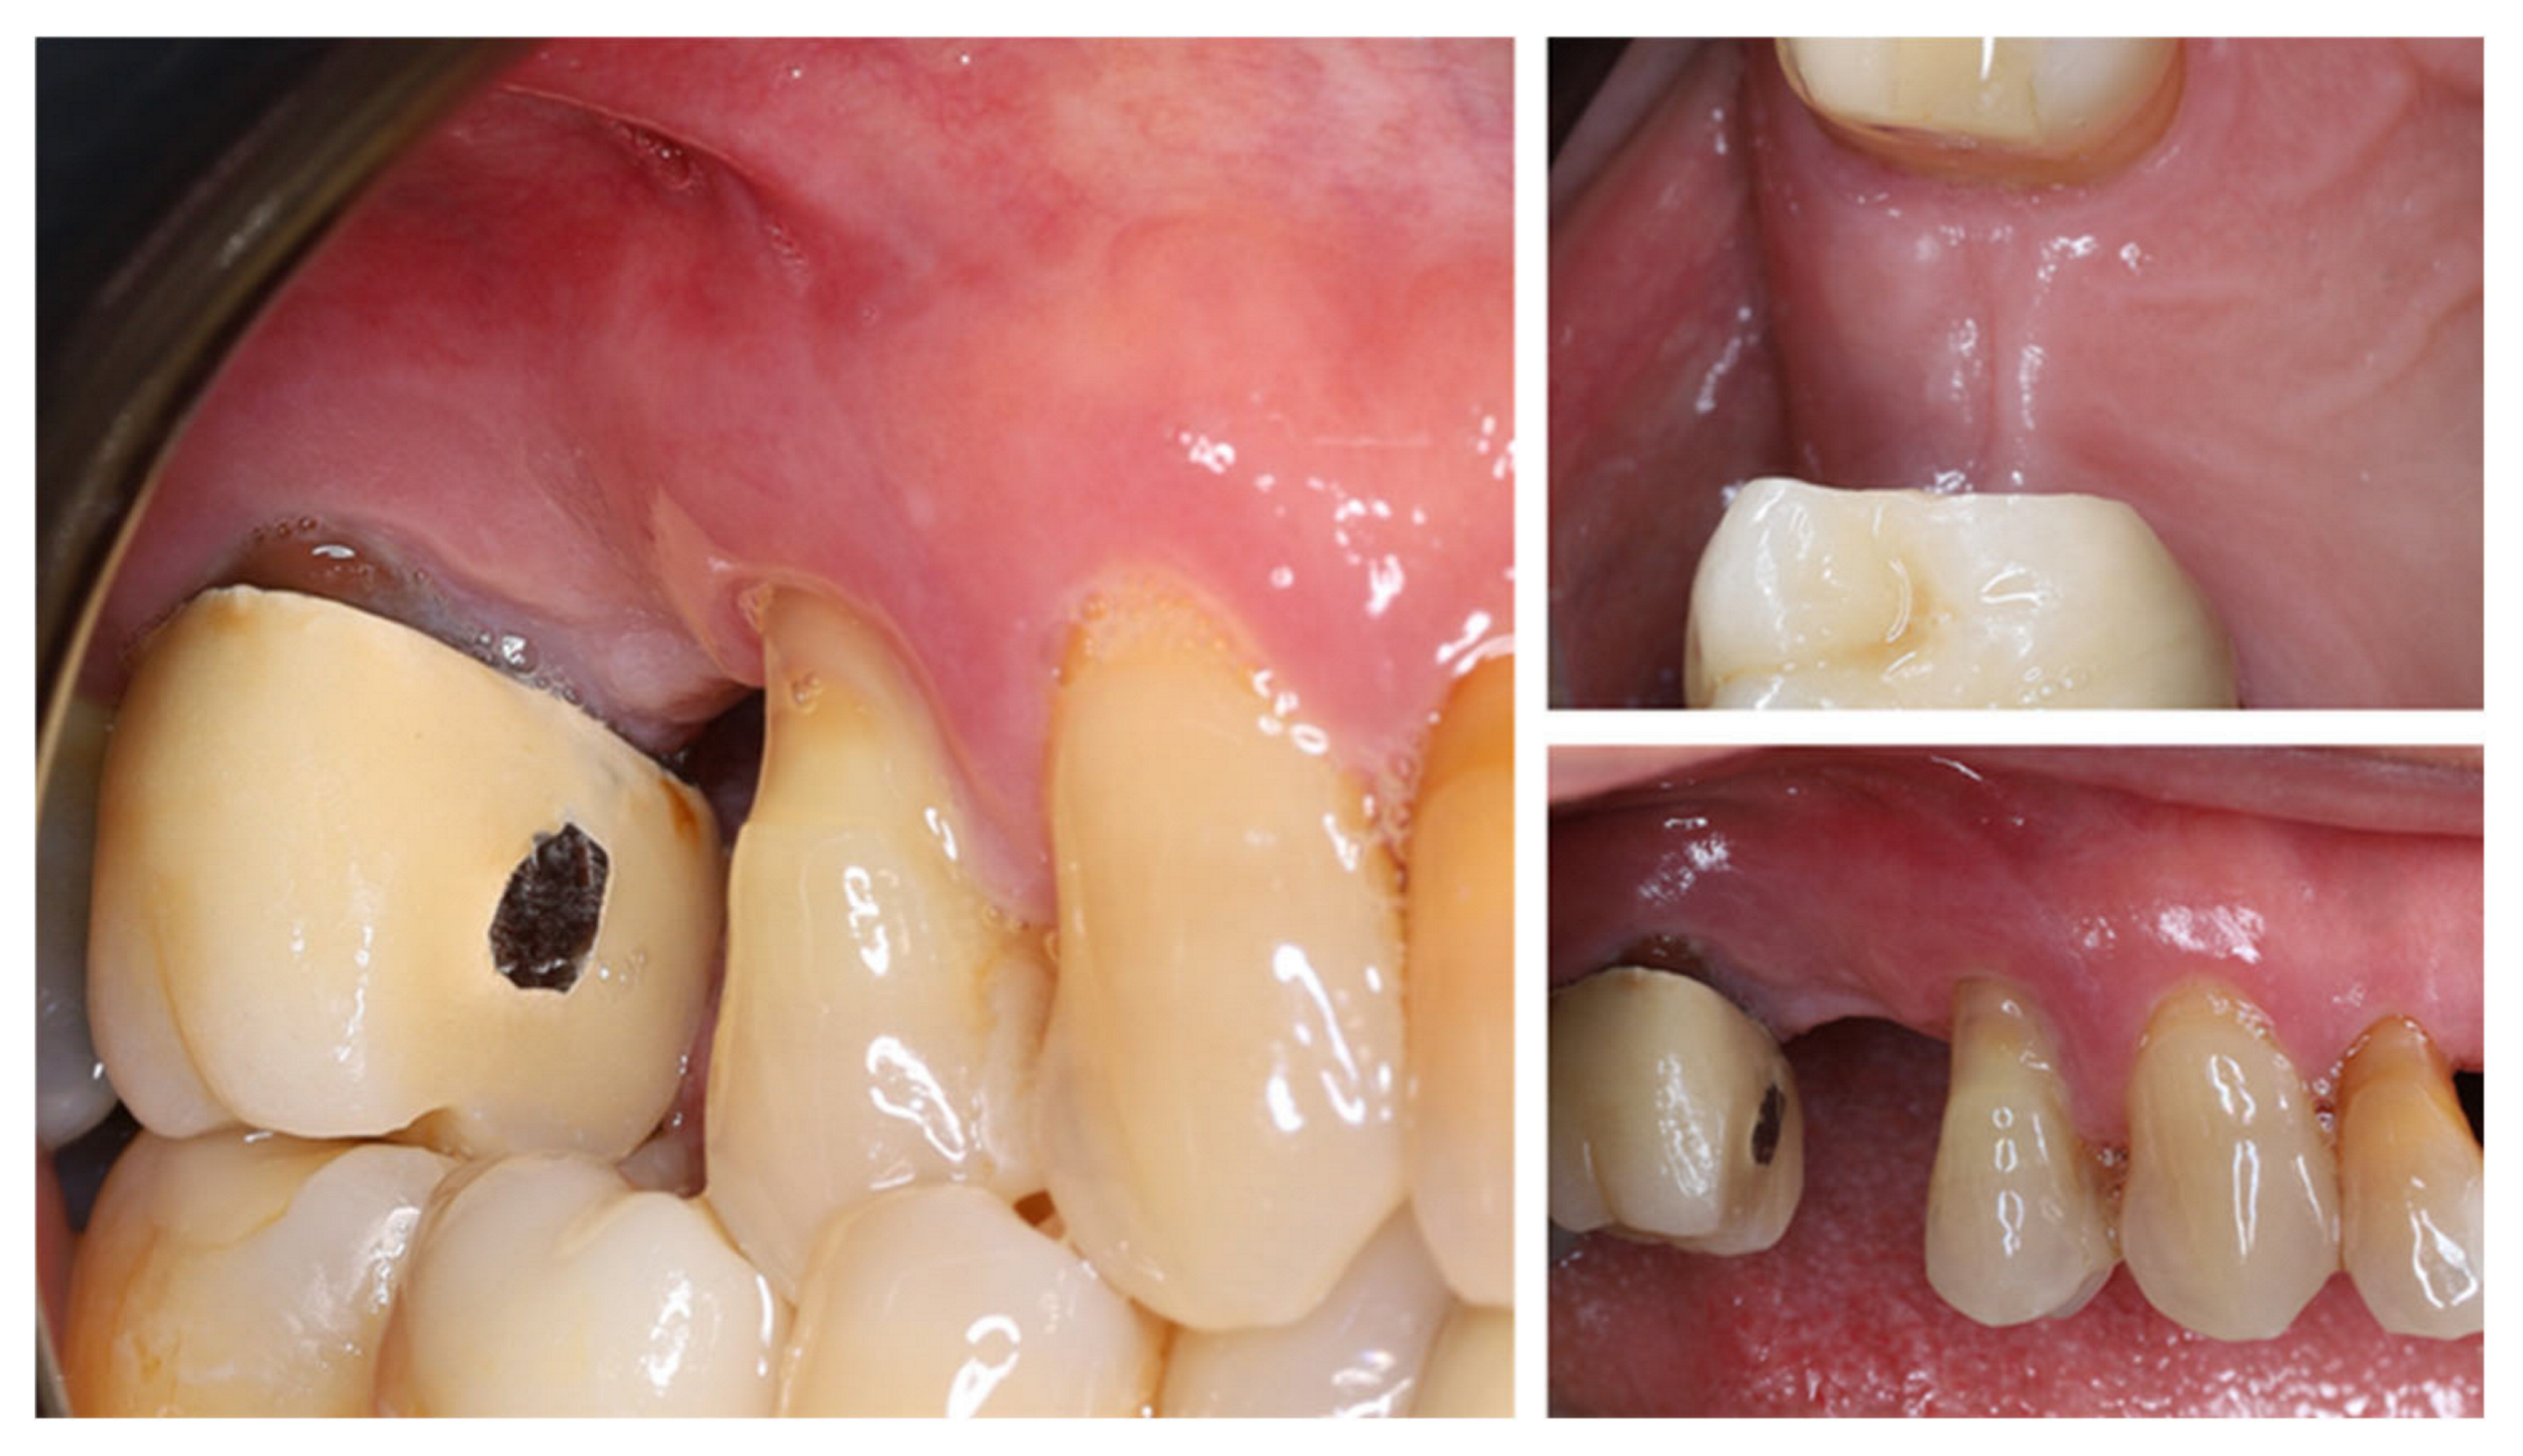

One year after tooth extraction, the clinical examination revealed complete soft tissue healing (Figure 3). At the buccal aspect of the alveolar ridge, the usual post-extraction horizontal ridge defect was observed. Post-extraction alveolar ridge collapse is a common clinical condition after tooth extraction. Horizontal and vertical bone loss can reach up to 60% within 2 years after tooth extraction, with most occurring within the first year after extraction.

Figure 3.

Clinical status of the patient after healing—vestibular and occlusal view.

This volume loss is most pronounced in the bucco-lingual direction and occurs more frequently in the absence of adequate buccal wall thickness of the dental alveolus (<1 mm) [24].